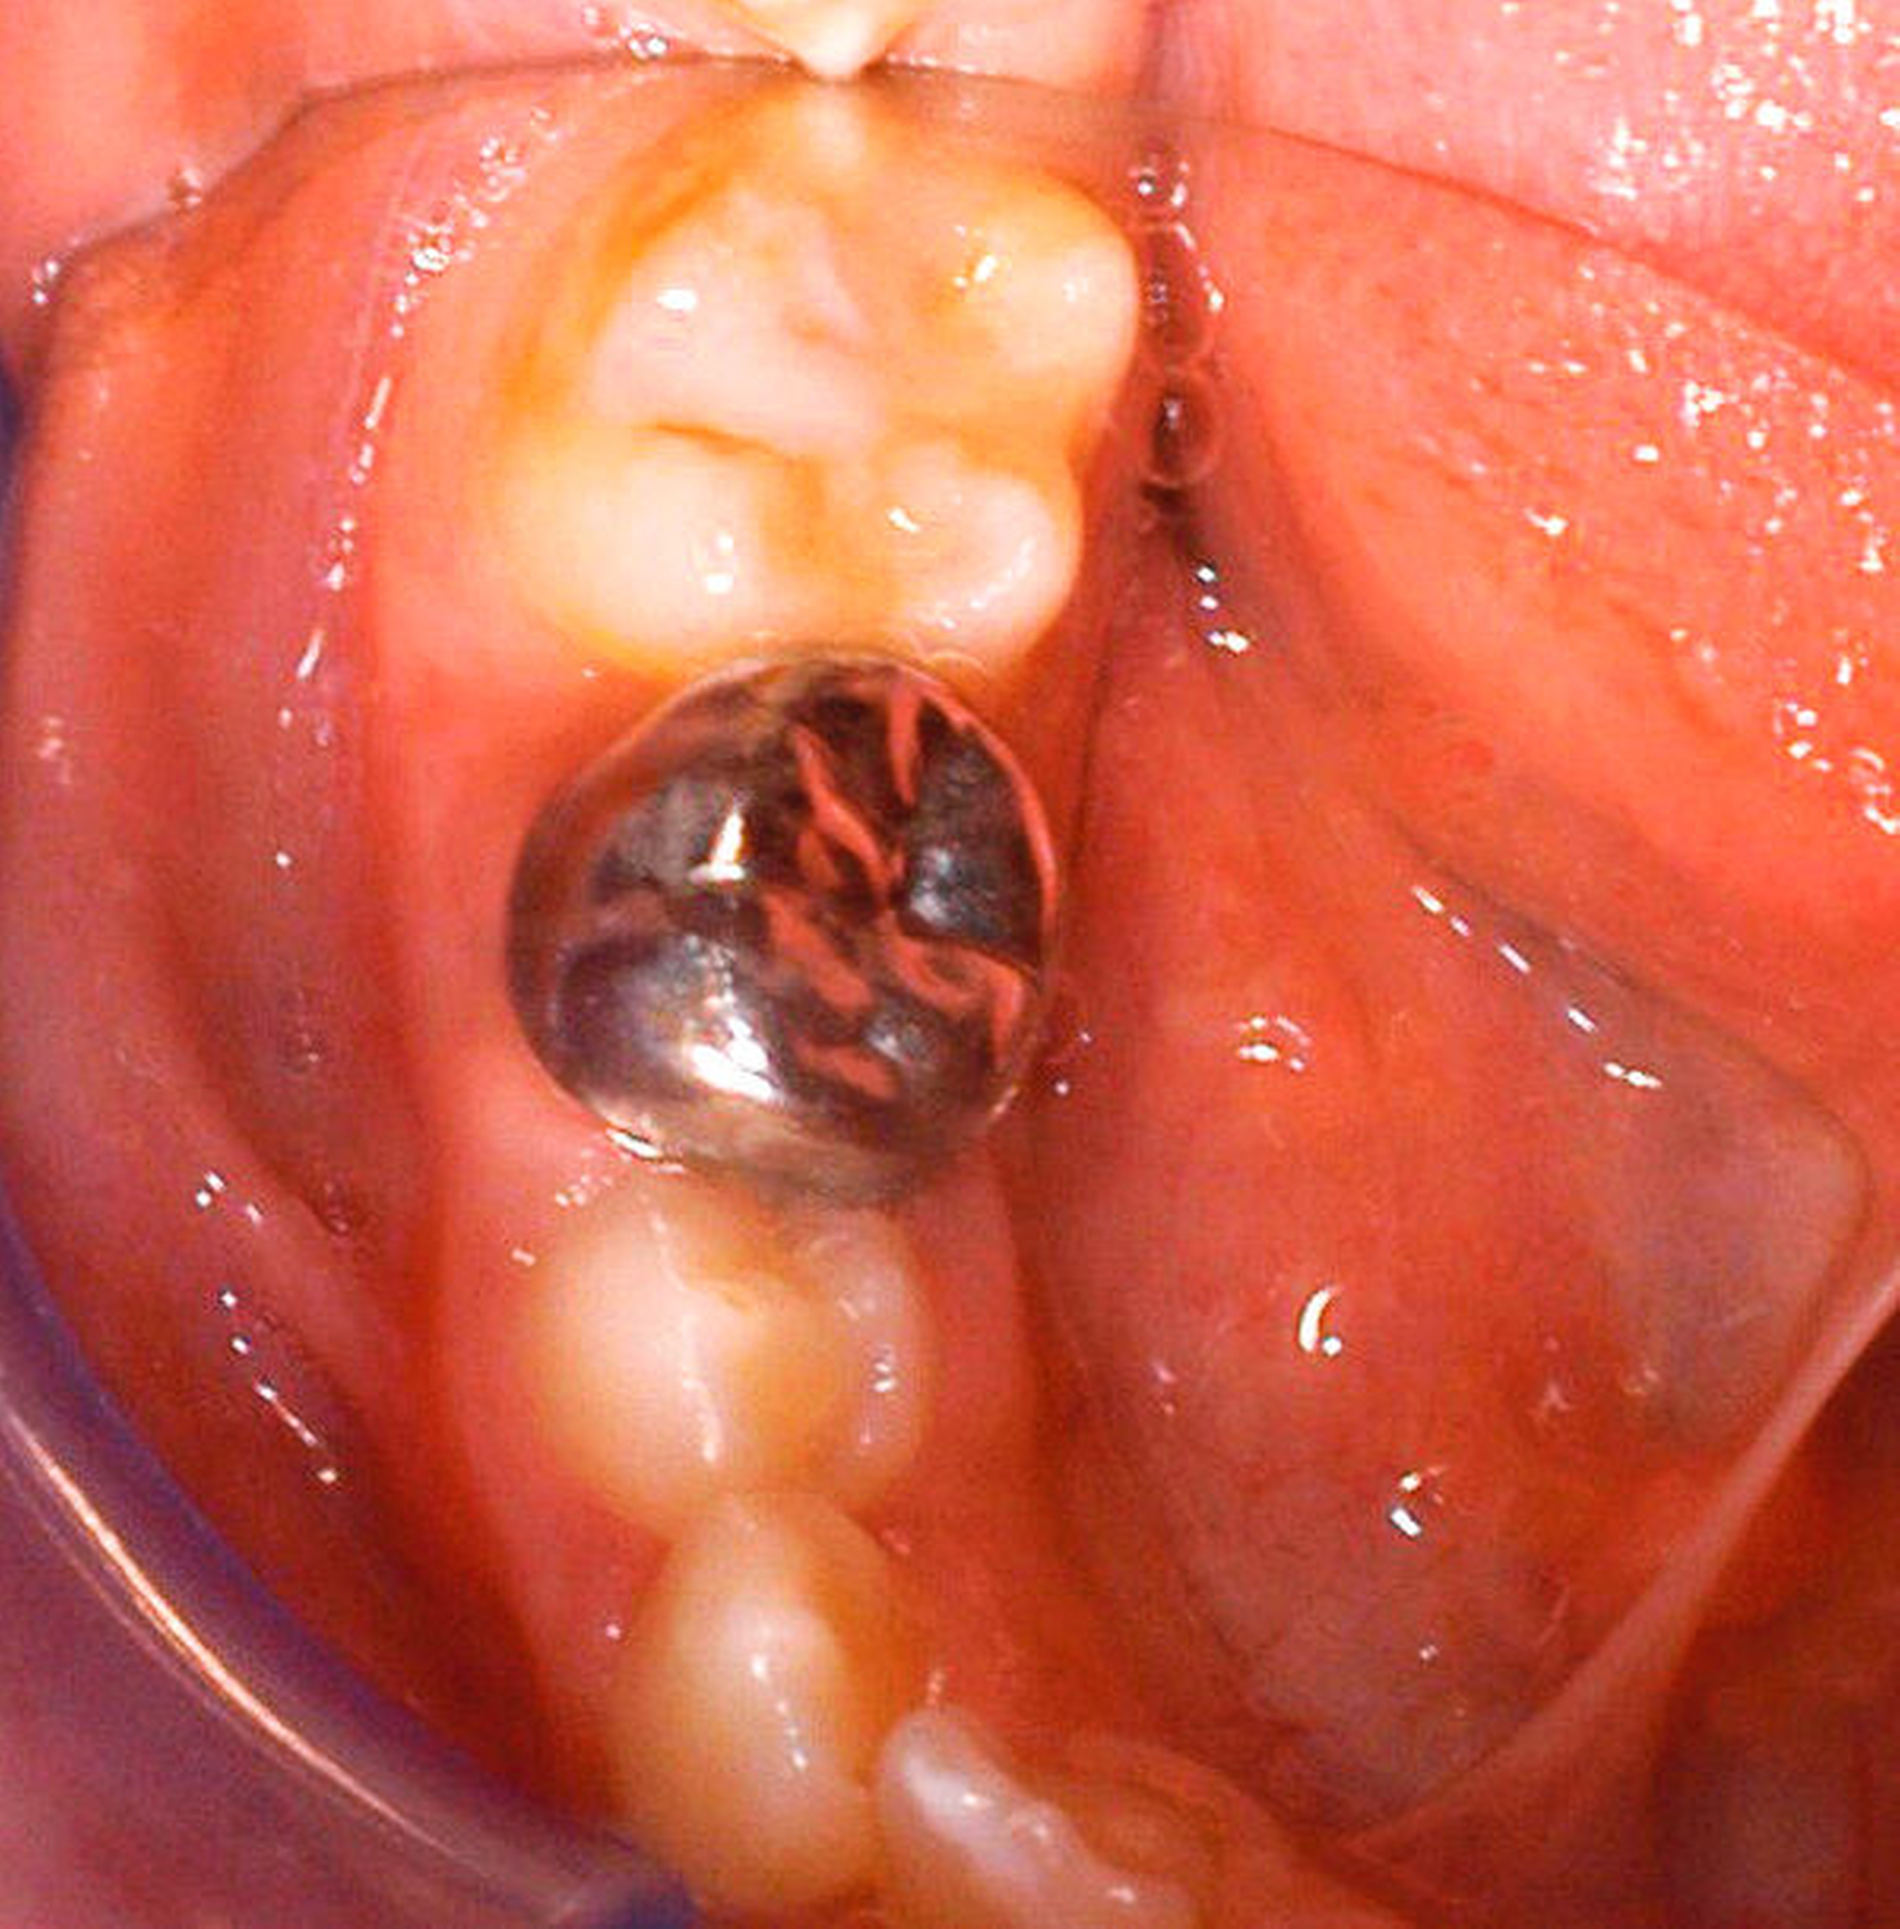

Während im Fall von minimalen Schmelzdefekten vorübergehend auch nur eine Verlaufskontrolle angezeigt sein kann, ist bei moderaten und ausgeprägten Einbrüchen die direkte Füllungstherapie indiziert. Für die Erstversorgung von MIH-Molaren, bei denen aufgrund einer unvollständigen Eruption keine absolute Trockenlegung möglich ist, eignen sich Glasionomerzemente (Abbildung 18). Langfristig sollten diese später durch definitive Füllungen ausgetauscht werden [Jalevik und Klingberg, 2002]. Bei leichten bis mittleren Defekten sind Komposite ein gutes Therapiemedium (Abbildung 19). Sie weisen bei adäquater Verarbeitung eine gute Haltedauer auf [Lygidakis et al., 2003]. Um einem weiteren Zahnhartsubstanzverlust vorzubeugen, sollten die Füllungsränder komplett im gesunden Schmelz liegen [Lygidakis et al., 2003]. Dafür muss allerdings der gesamte defekte Schmelz entfernt werden. Leider besteht hier für den Behandler oft die Schwierigkeit, das Ausmaß der Präparation festzulegen, da die hypomineralisierten Areale manchmal schwierig zu bestimmen sind. Zum anderen ist dies mitunter aufgrund der großflächigen Ausbreitung der Mindermineralisation nicht praktikabel. In diesen Fällen ist ein primär minimalinvasives Vorgehen vorzuziehen, verbunden mit periodischer Kontrolle der gelegten Füllung [Kellerhoff und Lussi, 2004]. Bei der Wahl des Adhäsivsystems sollte den Self-Etch-Adhäsiven der Vorrang gegeben werden. Sie zeigen in Laboruntersuchungen bessere Haftwerte als Total-Etch-Systeme an hypomineralisierten Zähnen – auch wenn diese immer noch geringer ausfallen als die gewohnt hohen Haftwerte an gesundem Schmelz [William et al., 2006].

Bildgruppe Abb. 15–22:Versorgungsbeispiele verschiedener Grade des MIH-Treatment-Need-Index